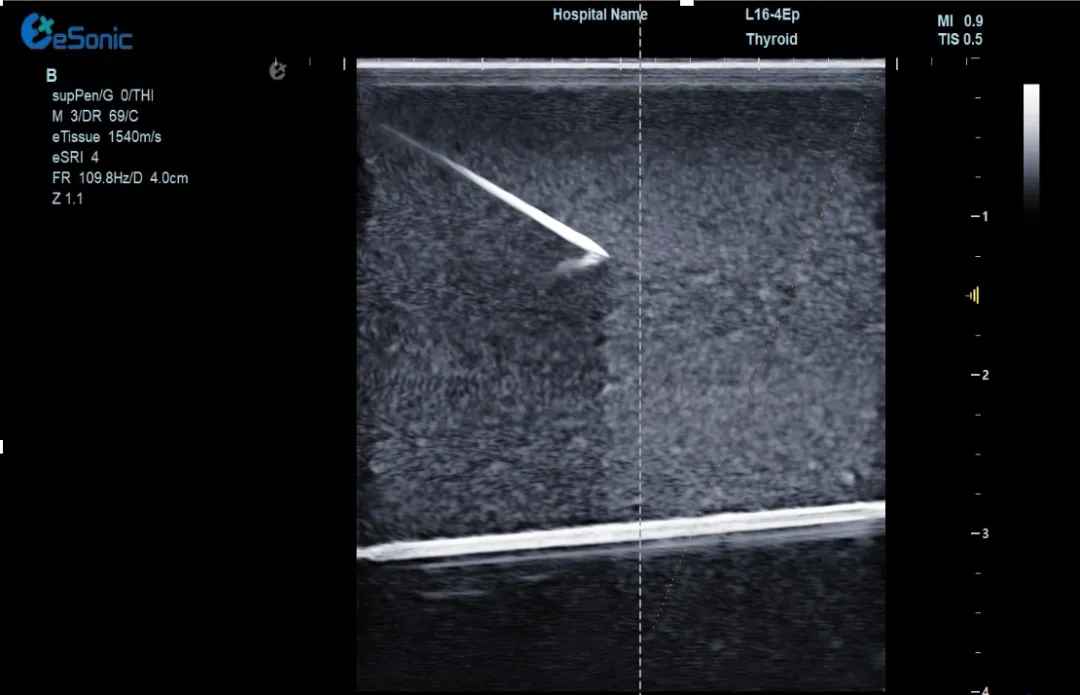

甲状腺篇

甲状腺结节患者也能从射频消融中受益。甲状腺是我们重要的内分泌器官,传统手术切除可能会影响甲状腺功能,还会在脖子上留下明显疤痕。射频消融就不一样了,它不仅能消除结节,还能很好地保护甲状腺功能,而且创口极小,几乎看不到疤痕,对爱美的人士十分友好。

640 (1)jia、.jpg

一位36岁的李女士在一次体检中,被查出甲状腺有结节,进一步检查后,虽确定结节是良性的,但较大的尺寸还是给她带来了吞咽异物感等不适症状。经过多方咨询和慎重考虑,李女士决定接受甲状腺射频消融治疗。

治疗当天,超声介入科董刚教授将一根细细的消融针穿刺到甲状腺结节内,通过针尖产生热量,高温加热作用可以使结节病灶组织被精准灭活,最后坏死组织随着时间的推移逐渐被身体吸收,直至消失。

640 (3) (2).gif

(甲状腺结节射频消融动态视频)

李女士接受了甲状腺射频消融手术,过程顺利,手术耗时约20分钟,患者无出血、声音嘶哑等并发症。术后生命体征正常,观察几小时后便回家休息。次日恢复正常生活,颈部几乎看不到明显伤口。复查时显示甲状腺结节缩小,吞咽异物感消失。术后李女士摸着几乎无痕的颈部笑到:“没想到20分钟就解决了困扰我几年的问题!为微创射频消融技术点赞!”